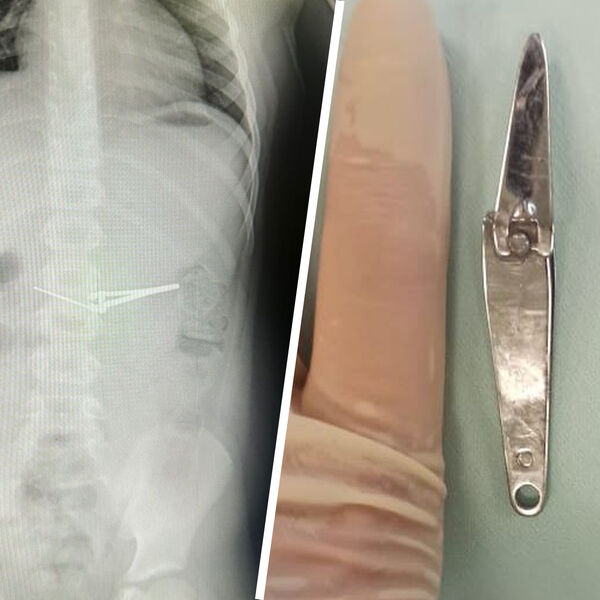

Щипцы для стрижки ногтей извлекли из желудка ребенка в Уфе

В Башкирии шестилетний ребенок проглотил щипцы для стрижки ногтей

Медики городской детской больницы №17 Уфы вытащили из желудка ребенка щипцы для стрижки ногтей. Об этом сообщает минздрав республики.

Инородное тело извлекали с помощью специальной эндокорзины, щипцы смогли подхватить и извлечь из желудка шестилетнего мальчика, не повредив при этом слизистую оболочку. Вмешательство проводилось под общим обезболиванием.